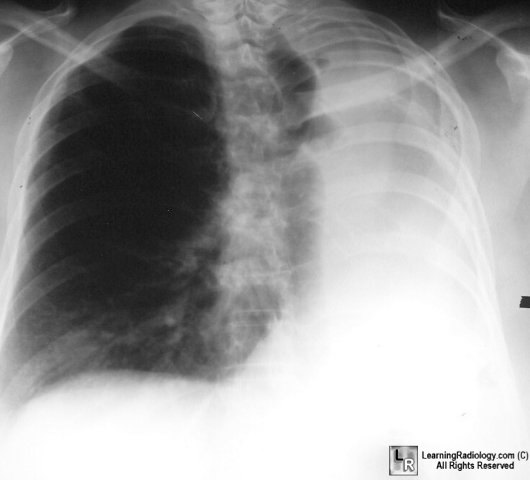

Pictorial Differential Diagnoses

Click on the tabs to see the differential; click on the photo to enlarge;

click on the text beneath the photo for more information

Pulmonary Differentials